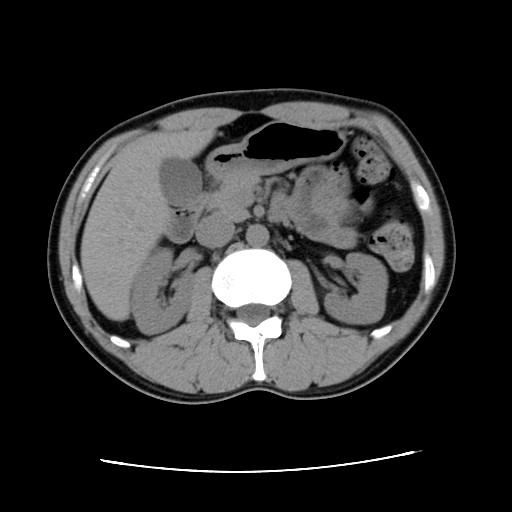

問題なし 【腫瘍マーカー】 HCGβ:<0.1 問題なし 【中性脂肪】 219→137 基準内(38-193)に入った 今回、検査画像をデータでもらってきた。 後腹膜の転移した箇所の前後4枚を2003年から2010年まで並べてみた。 http://gomatsushita.gozaru.jp/ct/album/index.html 2006/7/18の画像を見ると腫瘍がハッキリ見える。 BEP2クール後の9/27の画像では明らかに縮小もしくは消滅。

【単純CT】

問題なし! 【腫瘍マーカー】 HCGβ:<0.1 問題なし! 先週検査でした。 今日はその結果。 今日は珍しく先生が寝ぼけていました(笑)。 次回のレントゲン検査の受付票を何回も出し間違えた。 1回目:診察後清算も済み帰ろうとした所で俺が気がついた。「これ、画像データCDR作成申込書じゃん・・・」 2回目:受付で上記を伝え、看護婦さん:「すいませ~ん!これで大丈夫ですか?」 確認すると今度はXP検査受付票なので「OKです!ありがとうござ・・・ん?!?これ検査日が今日です・・・・」 看護婦さんダッシュで戻っていきました。 3回目:看護婦さん:「今度は~~」 俺:「間違いないです!」 看護婦さん:「先生寝ぼけてるんですよぉ~」 次は3月!